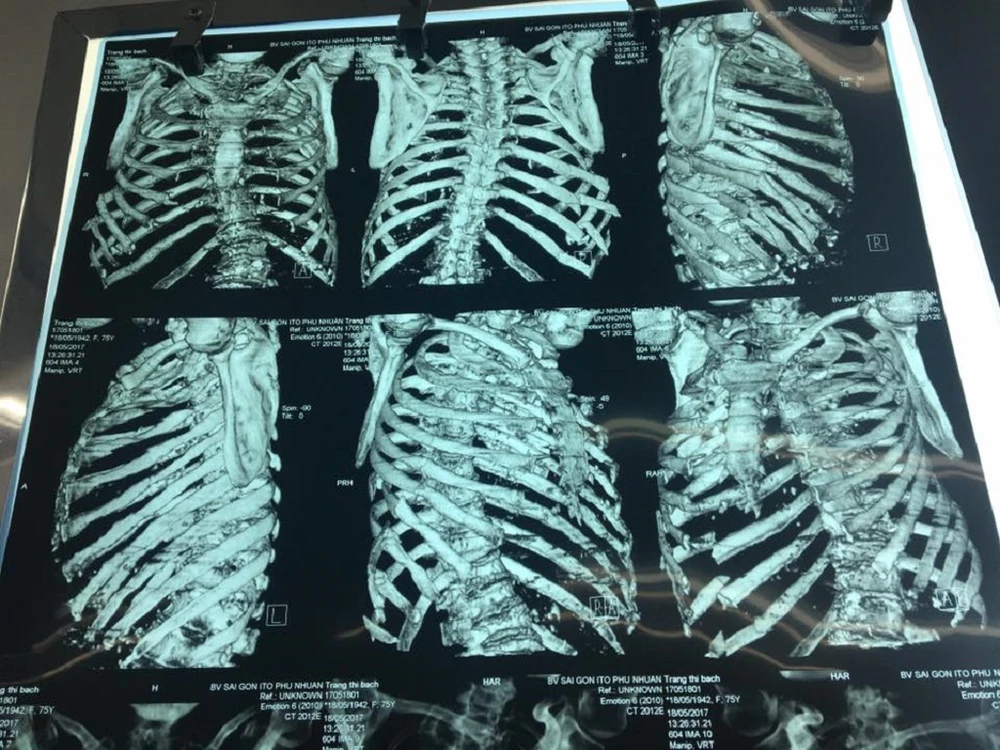

8 chiếc xương sườn của cụ B. bị gãy

Ngày 19-5, BS CKII Nguyễn Thành Tâm, Giám đốc BV Chấn thương Chỉnh hình Sài Gòn ITO (TP.HCM), cho biết bệnh viện vừa tiếp nhận cụ bà TTB được chuyển từ BV tỉnh Bà Rịa lên trong tình trạng nguy kịch vì mất quá nhiều máu. Bệnh nhân khó thở vì tràn dịch màng phổi bên phải, gãy 8 xương sườn, gãy xương đùi phải và theo dõi tình trạng chấn thương gan.

Các bác sĩ nhận định nếu không phẫu thuật sớm, bệnh nhân có thể tử vong vì mất máu và chèn ép đường thở. Các bác sĩ đã tiến hành gấp ca phẫu thuật dẫn lưu phổi, truyền máu, thực hiện kỹ thuật đặt giảm đau ngoài màng cứng, cố định xương đùi. Sau phẫu thuật, cụ bà đã qua cơn nguy kịch, sức khỏe ổn.

“Sau một tuần, nếu sức khỏe diễn tiến tốt, bệnh nhân sẽ được mổ xếp lại xương đùi. Riêng 8 cái xương sườn bị gãy, tạm thời chưa thể mổ do cần theo dõi thêm. Cụ bà thể trạng gầy yếu, tuổi cao mà chịu nhiều chấn thương nặng, mất máu nhiều nên ưu tiên các kỹ thuật cứu sống bệnh nhân trước. Các tổn thương cơ xương khớp sẽ tiến hành từng bước” -  BS Tâm cho biết.